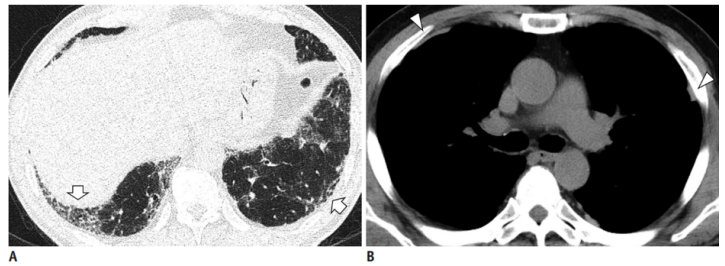

(1)感染性疾病:病毒性?细菌性?真菌?非典型病原体?吸入性肺炎?(2)非感染性疾病:心衰?急性肺栓塞?自身免疫性疾病?麻醉/手术相关肺损伤?急性间质性肺炎?回顾分析患者入院时胸部CT: 双肺靠近外周近胸膜处有轻微细小间质样改变(图4)。诊断:急性间质性肺炎;Ⅰ型呼吸衰竭;左肺下叶部分切除术后;高血压病。ECMO支持;呼吸机支持;甲泼尼松80 mg q12h,尼达尼布;镇静镇痛;抗感染;营养支持。ECMO第6天, 术后第18天, 肺部病变进一步加重(图5)。血气分析: pH 7.543, PaO2 154 mmHg, PaCO2 33.2 mmHg(ECMO, FiO2 100%, MV FiO2 60%)。术后第26天复查胸部CT未见改善。患者最终死亡。笔者团队也曾接诊过一例早期肺癌患者,2013年和2014年随访肺部结节均无明显变化。2015年胸部手术后2天,两肺变白(图6)。当时医生警惕性非常高,立刻行胸部CT检查并予相应治疗,患者最终存活。2022年RadioGraphics 杂志报道一例85岁女性腺癌患者奥希替尼治疗5个月后。图7-A和B为治疗前胸部CT图像,可见右肺中叶有肿块(A中箭头)。胸膜下区域磨玻璃改变和网状结构(箭头)提示存在间质性肺异常(Interstitial Lung Abnormalities,ILA)。治疗5个月后的轴位CT图像显示肿块(C中白色箭头)、弥漫性磨玻璃改变和合并症(黑色箭头)。图源:Radiographics, 2022, 42(7):1925-1939.另一例66岁右上肺鳞癌患者,术前CT显示肿块(图8-A中箭头)位于肺右上叶。轻度磨玻璃改变(箭头),提示ILA,见于胸膜下区域。图8-C和D为术后CT,显示弥漫性磨玻璃样改变和实变(箭头),牵引性支气管扩张症(图8-C中箭头),也可见胸腔积液(图8-D中箭头)。图源:Radiographics, 2022, 42(7):1925-1939.